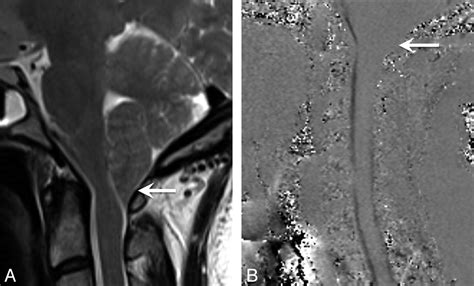

Cine Flow MRI Analyzes the velocity and volume of cerebrospinal fluid (CSF) flow.

The flow of cerebrospinal fluid is the "pulse" of the central nervous system. It acts as a shock absorber and clears waste products from the brain. In patients with Cerebellar Tonsillar Ectopia, the displaced tonsils may partially obstruct the narrow space where the CSF exits the skull. This blockage can create a bottleneck effect, leading to pressure buildup. When the fluid cannot circulate freely, it may lead to the formation of a syrinx—a fluid-filled cyst within the spinal cord—which can cause further neurological damage if left unaddressed.